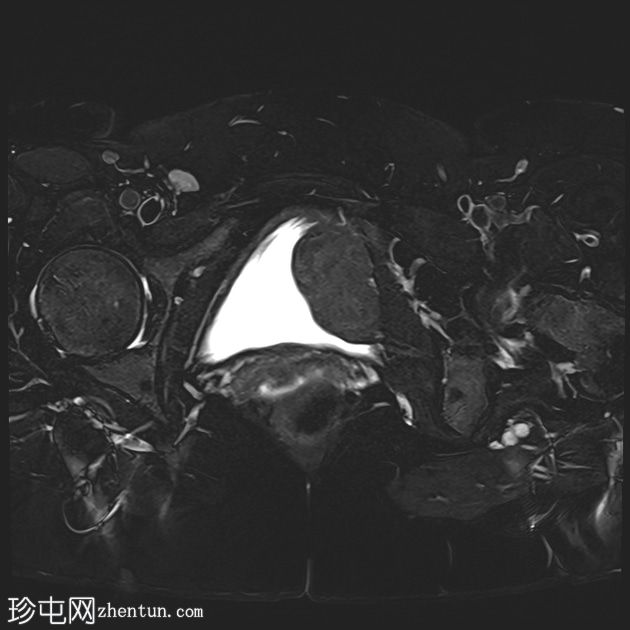

MRI

轴位

T2加权像

可见膀胱左侧壁有一边界清晰的T2低信号实

性病

灶,无扩散受限,均匀强化。未见膀胱周围侵犯或肾积水。

子宫底部前壁可见一小肌瘤。双侧卵巢可见无强化囊肿。盆腔及腹股沟未见异常淋巴结肿大。

这是一例经组织学证实的膀胱平滑肌瘤病例。